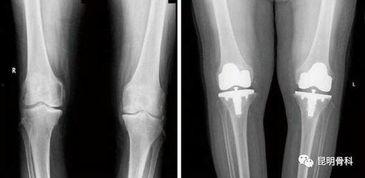

首先,得先给你科普一下什么是膝盖置换手术。简单来说,就是将受损的膝关节替换成人工膝关节,让患者重新拥有健康的关节。而国产膝盖置换,顾名思义,就是使用我国自主研发的人工膝关节进行的手术。

c. 安装人工膝关节:将人工膝关节安装到患者膝关节处。